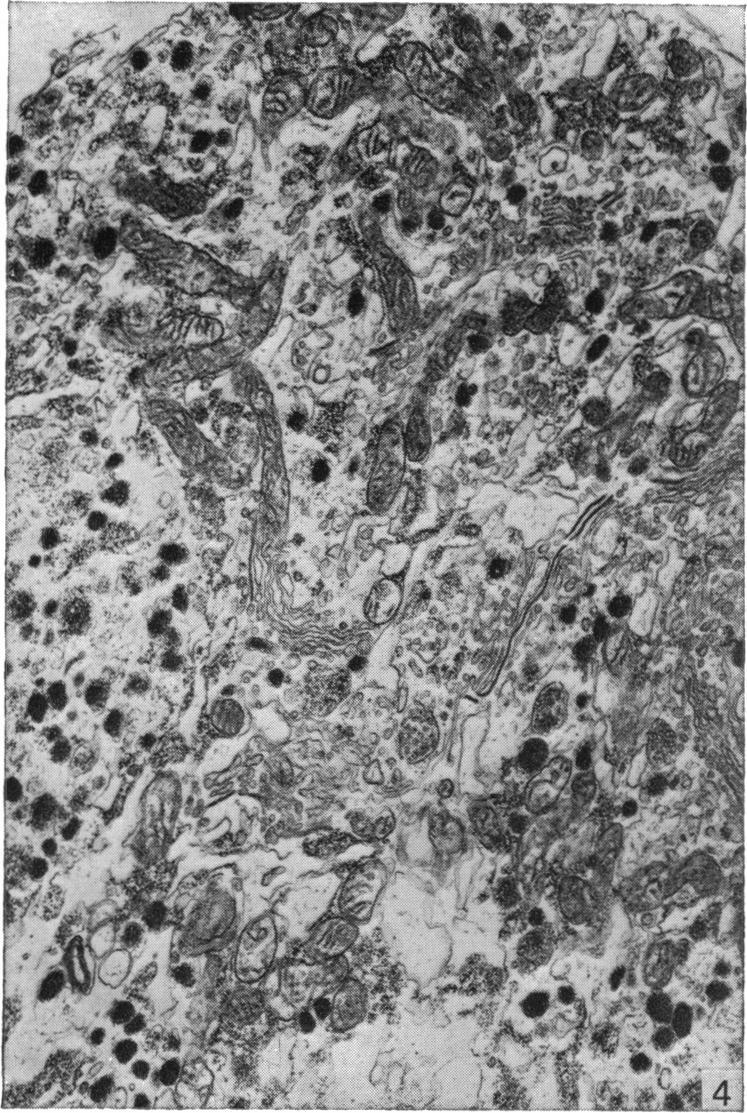

A technique is described which permits the maintenance for up to 8 days in organ culture of explanted rat pituitary glands. Electron microscope studies showed that the cultured glands (whether treated with gonadotrophin-releasing hormone (GnRH) or not) were almost identical to controls in appearance, although the stellate (follicular) cells seemingly were eliminated in vitro. Gonadotrophs and prolactin-secreting cells in male and female pituitary glands were similar in appearance both in vivo and in vitro to comparable cells described by other authors. There was some evidence for an increase in the secretory activity of these cell types (particularly gonadotrophs) when the explants were treated with GnRH. The present technique thus provides a suitable and valid 'model' with which to study the effects of GnRH and steroid hormones on the release and synthesis of FSH and LH in vitro.

本文描述了一种技术,该技术可使离体大鼠垂体腺在器官培养中维持长达8天。电子显微镜研究表明,培养的腺体(无论是否用促性腺激素释放激素(GnRH)处理)外观上与对照几乎相同,尽管星状(滤泡)细胞似乎在体外被清除。雄性和雌性垂体腺中的促性腺激素细胞和催乳素分泌细胞在体内和体外的外观与其他作者描述的同类细胞相似。有证据表明,当外植体用GnRH处理时,这些细胞类型(特别是促性腺激素细胞)的分泌活性会增加。因此,本技术提供了一个合适且有效的“模型”,用于研究GnRH和类固醇激素对体外FSH和LH释放与合成的影响。